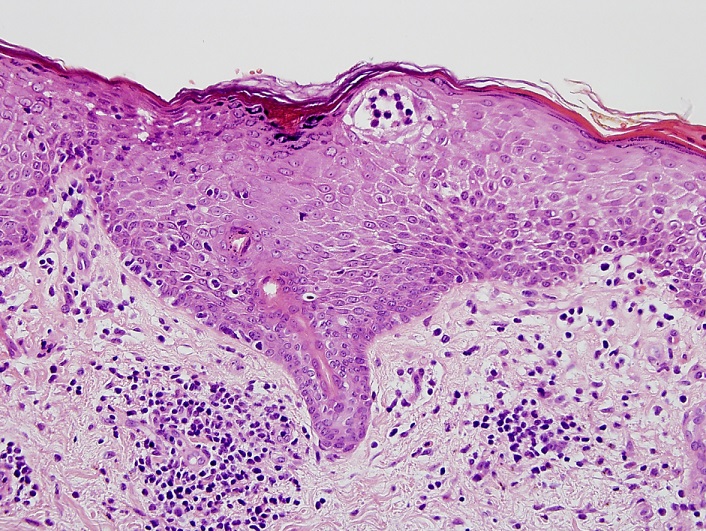

Image: sparse infiltrate with epidermotropism (courtesy of Dr Julia Scarisbrick)